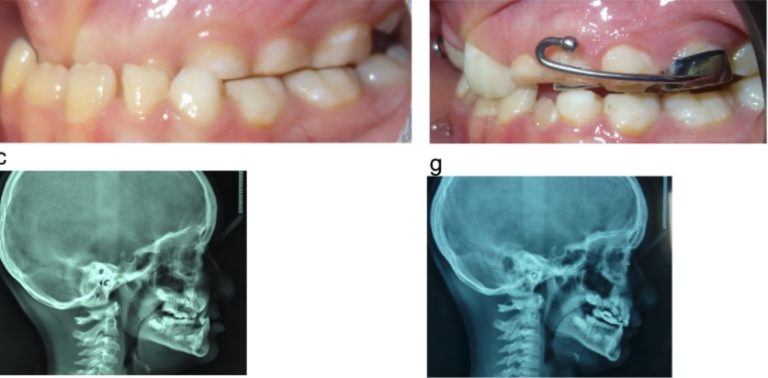

Tratamiento ortopédico de una maloclusión de clase III con mordida cruzada anterior profunda y discrepancia transversal

El artículo que compartimos el día de hoy con uds se llama Orthopedic Management of a Class III Malocclusion With Deep … [Leer más...] acerca de Tratamiento ortopédico de una maloclusión de clase III con mordida cruzada anterior profunda y discrepancia transversal